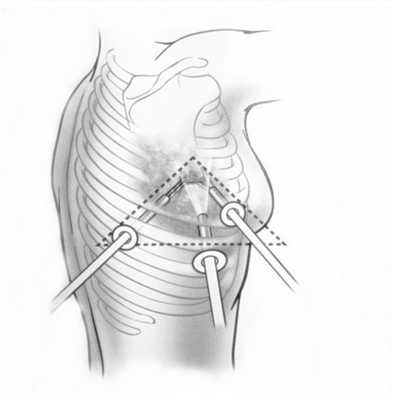

При невозможности получить образец ткани для исследования эндоскопически применяются инвазивные методы: трансторакальная биопсия, медиастиноскопия, видеоторакосокпия. Последние два метода — это серьезные операции, которые проводятся в специализированных медицинских учреждениях.

Поскольку тактика лечения лимфомы средостения определяется гистологическим и иммуногистохимическим типом опухоли, то обязательным этапом диагностики является биопсия. При увеличении доступных для пальпации лимфоузлов проводят эксцизионную, пункционную или прескаленную биопсию. В остальных случаях прибегают к операционной биопсии с помощью медиастиноскопии, парастернальной медиастинотомии, диагностической торакоскопии.